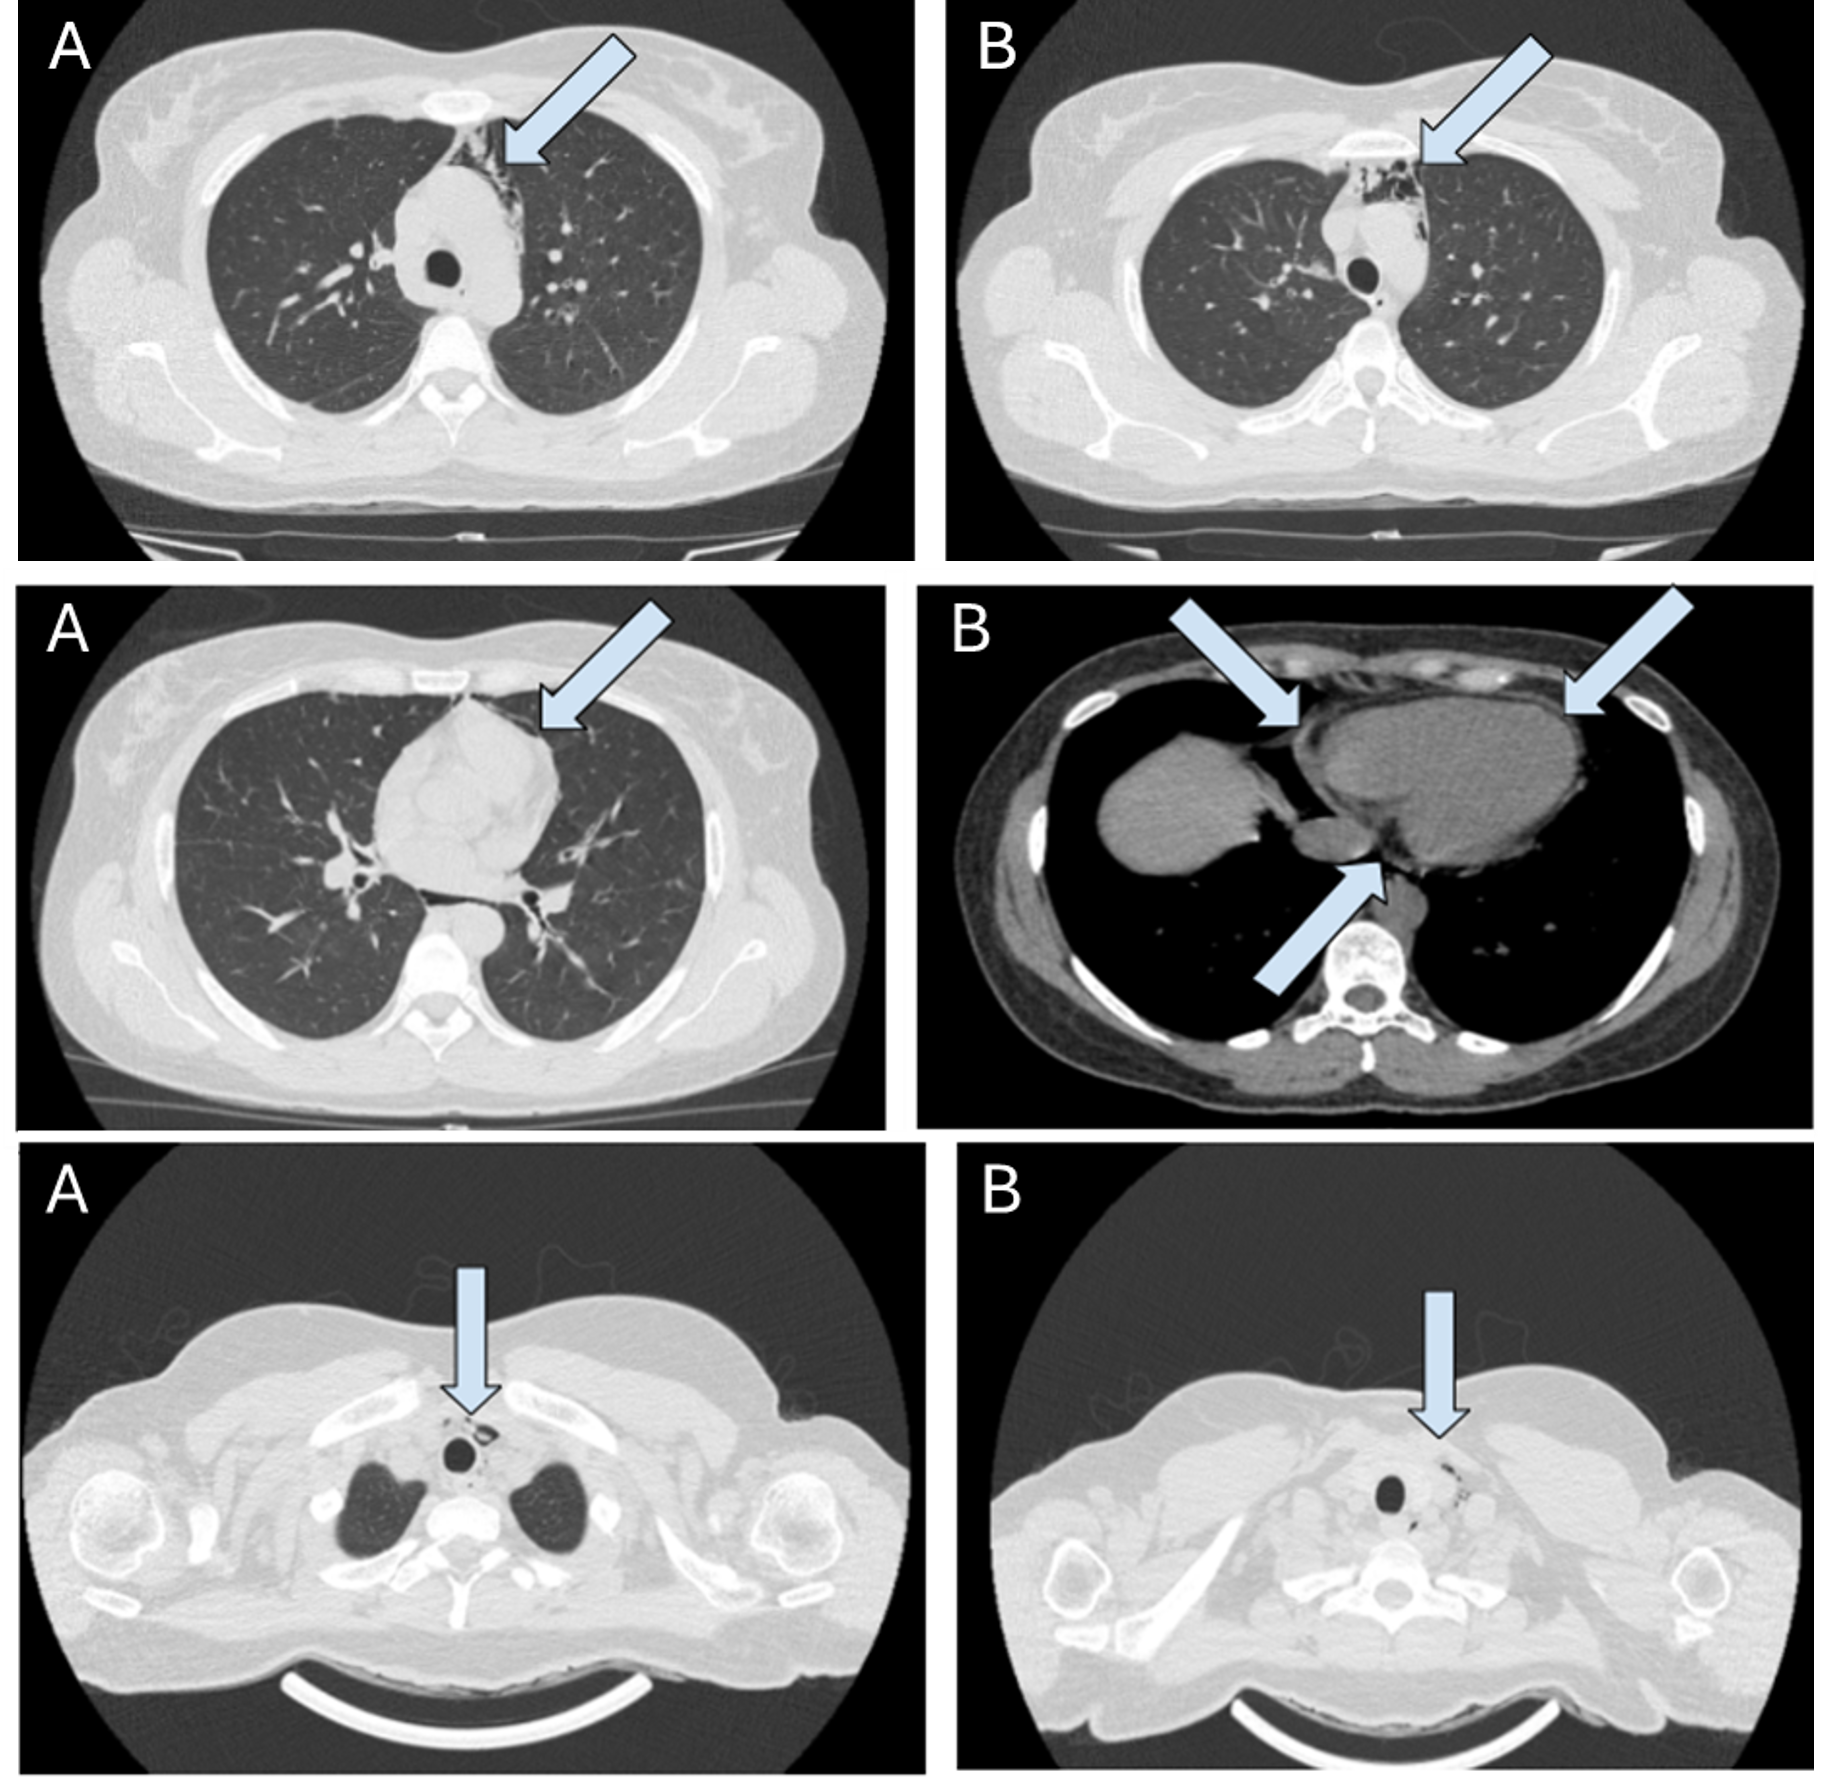

The Crack Lung – A Case Report

Débora Lopes, Cátia Gorgulho, Joana Ribeiro, André Neto Real, Nuno Catorze

bjcr49

When Pulmonary Tuberculosis Leads to Pneumothorax: An Unusual Presentation

Catarina Bettencourt Giesta, Manuel d'Almeida, Sara Pires Ferreira

bjcr50